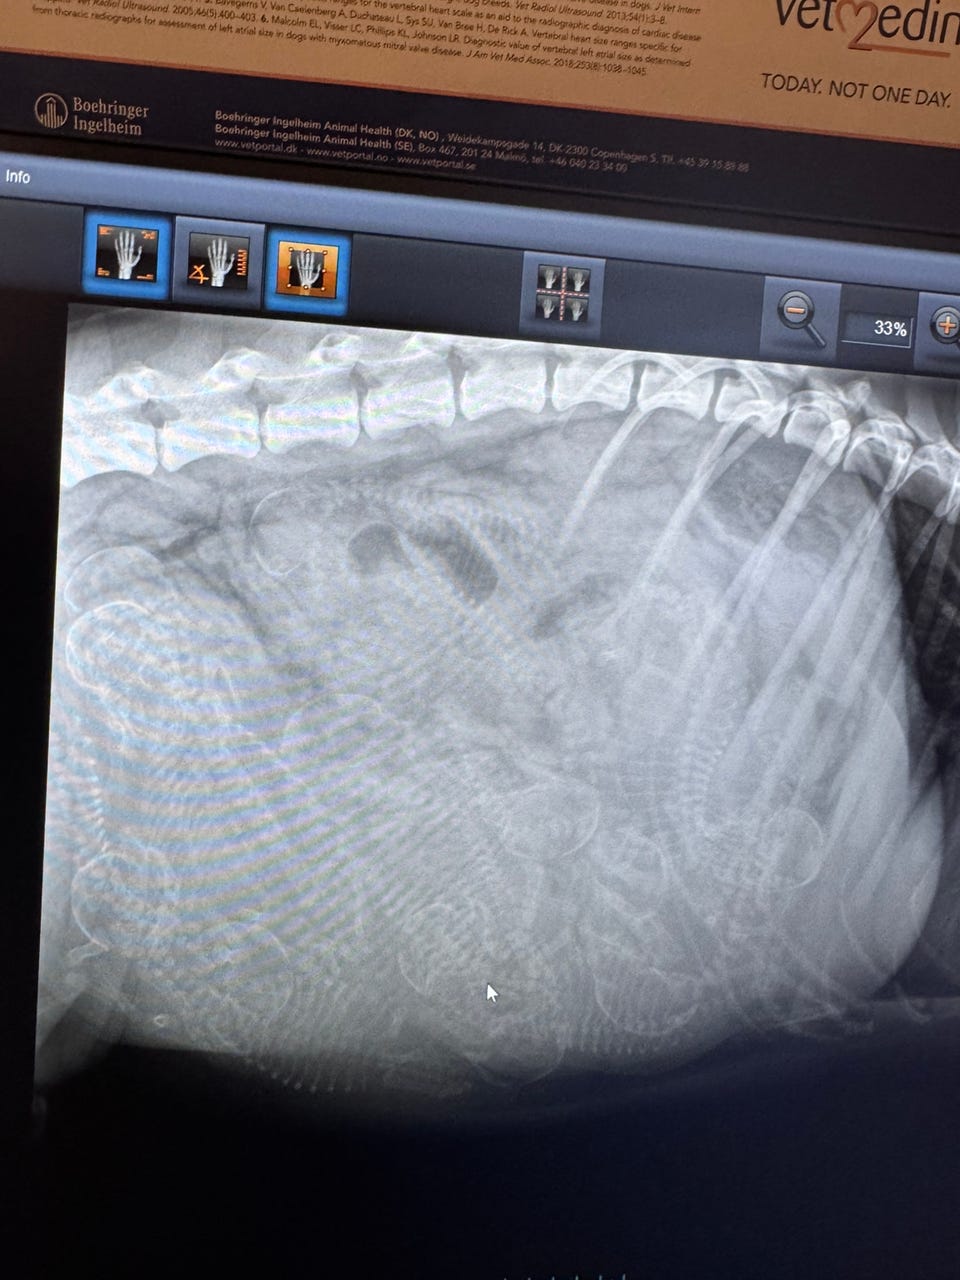

- Røntgen: fri for HD og AD